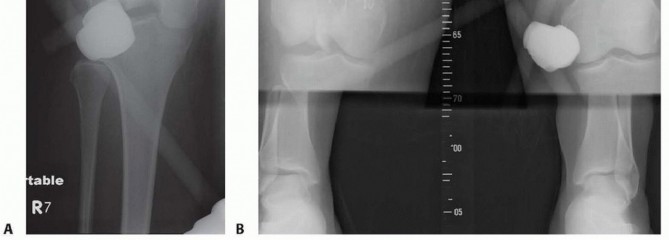

### TECH FIG 10 • A. Closure of the arthrotomy. B,C. Full flexion and extension of the knee after definitive fixation and closure. As seen in final AP (D) and lateral (E) radiographs, the metaphyseal comminution is bridged and left undisturbed. - Standard Wound Closure Closure of the arthrotomy is performed with figure-8 0 Vicryl sutures. This is reinforced by a running 2-0 FiberWire (Arthrex, Inc., Naples, FL) or Ethibond suture ( TECH FIG 10A). The subcutaneous tissue is closed with 2-0 Vicryl. The skin is closed with staples, as are the percutaneous stab incisions. The knee is flexed and extended fully to ensure restoration of motion as well as to break any adhesions in the quadriceps that may have formed while the temporary bridging external fixator had been in place ( TECH FIG 10B,C). The final radiographs are taken in the operating room ( TECH FIG 10D,E). 1. ## Open Reduction and Internal Fixation of the Distal Femur with Locking Plates (Type A or Nondisplaced Type C1 or C2) This technique can be used regardless of the locking plate system used. Each system's technique guide should be reviewed before use as each system has its own idiosyncrasies. Variations in plate application as well as reduction tools and techniques are unique to each system. See comments earlier regarding temporary use of an external fixator or distractor. ### Limited Lateral Approach A lateral incision measuring about 5 to 6 cm is made starting at the level of the joint and extending proximally in line with the shaft. The distal extent is curved slightly toward the tibial tubercle, as in the lateral approach ( TECH FIG 11A,B). The iliotibial band is incised in line with the skin incision ( TECH FIG 11C). The dissection is carried down to the lateral femoral condyle. The lateral aspect is exposed enough for plate placement ( TECH FIG 11D). A Cobb elevator is used to create a plane submuscularly up the lateral shaft of the femur for placement of the plate.

TECH FIG 11 • Patient with closed distal femur fracture (also shown in FIG 5G,H and 6C-E). A. Limited lateral incision, with the tibial tubercle marked. B. Skin incision showing the iliotibial band. C. Incision of the iliotibial band. D. Exposure of the lateral aspect of the femur. 487 ### Stabilizing the Articular Surface For nondisplaced type C1 or C2 fractures, the first priority is to stabilize the articular surface. Visualization of the joint may be accomplished with placement of a blunt Hohmann retractor (or similar Z retractor) ( TECH FIG 12A).

--- - TECH FIG 12 • (continued) G. Definitive fixation of the condyles with 4.5-mm partially threaded cannulated screws. Definitive fixation of the condyles should be performed (see technique description earlier) ( TECH FIG 12G). ### Reduction of the Distal Segment and Plate Placement Reduction of the distal segment to the shaft can be performed using temporary Steinmann pins ( TECH FIG 13). The plate can now be applied in a submuscular fashion (see Placement of the Plate section earlier). ### Wound Closure Final radiographs are taken in the operating room ( TECH FIG 14). Standard wound closure is undertaken, as described in the previous section. ### Retrograde Nailing(FIG 10A-F) Refer to Chapter 43 on retrograde nailing of the femur.

--- - TECH FIG 14 • A,B. Final AP and lateral radiographs reveal that the posterior and medial metaphyseal comminution is left undisturbed.